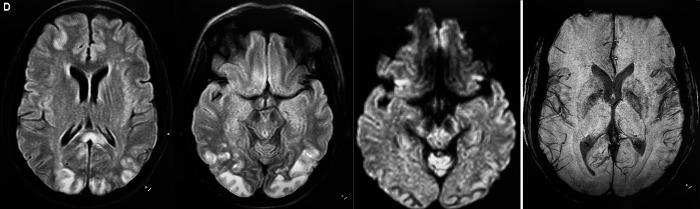

We report a case of a middle-aged female who presented with severe COVID-19 disease with no neurological symptoms. She complained of diminished vision on day 7 of the illness and underwent an MRI brain to rule out an ischemic stroke but the findings were suggestive of PRES. She had no episode of hypertension during the hospital stay. Probably severe COVID-related inflammation was the reason for such a presentation. Conservative management resolved the issue and her symptoms weaned off.

我们报告一例中年女性病例,该患者患有严重的COVID-19疾病,但无神经系统症状。她在患病第7天抱怨视力下降,并接受了脑部MRI检查以排除缺血性中风,但检查结果提示为PRES。她在住院期间未发生高血压。可能严重的COVID相关炎症是出现这种表现的原因。保守治疗解决了问题,她的症状逐渐缓解。